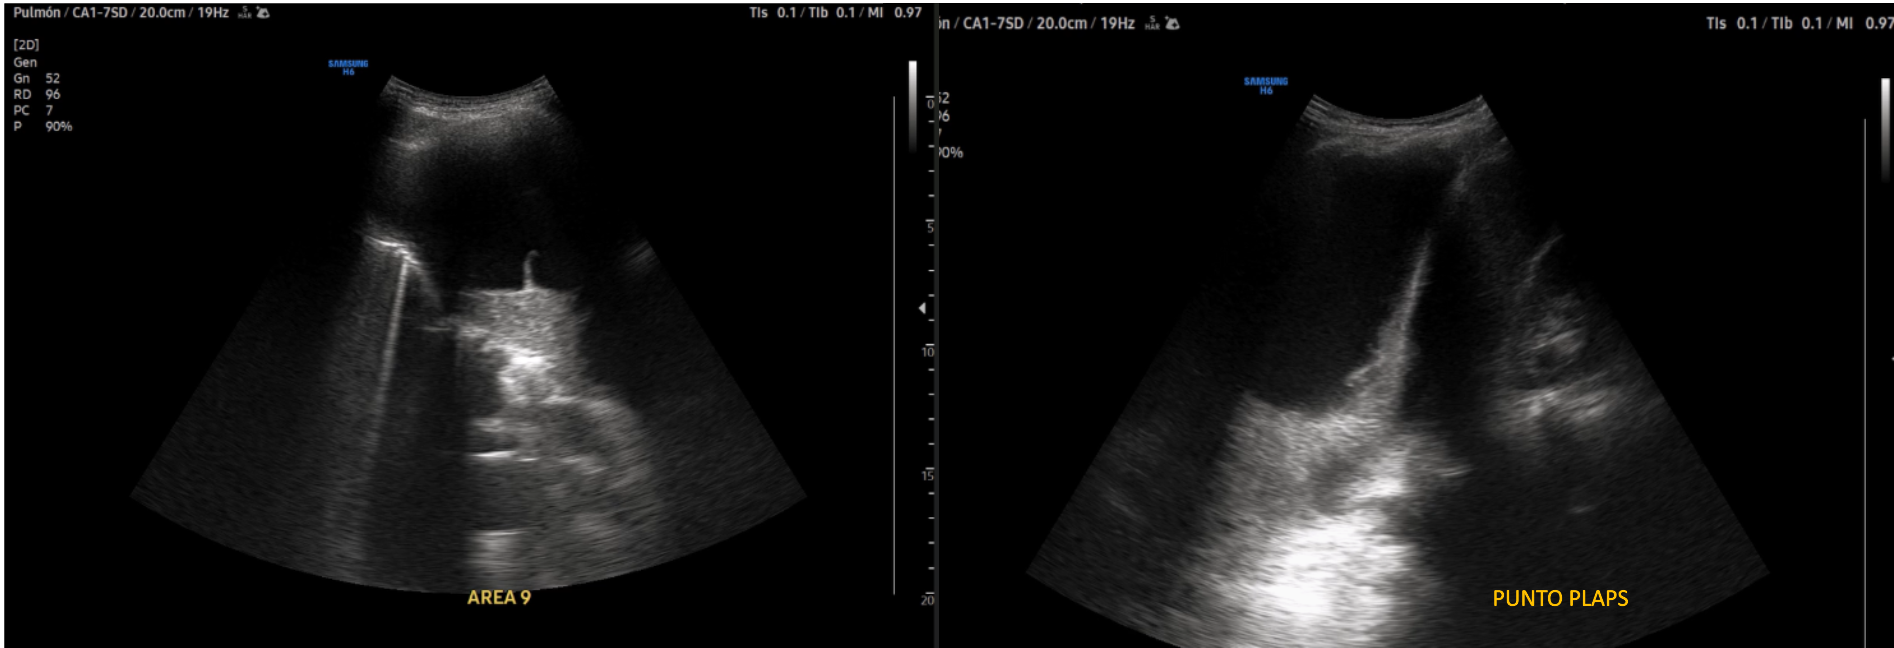

Realizamos Ecografía clínica pulmonar: imagen anecoica con septos finos y signo de la medusa compatible con derrame pleural tabicado con atelectasia en base derecha de aproximadamente 1150 ml por cuantificación de Goecke 2, en ápex líneas B finas. Campo pulmonar izquierdo líneas A.

Múltiples toracocentesis diagnósticas/evacuadoras total de 1,08 litros y con líquido pleural tipo exudado linfocítico; microbiología y citología negativa. Ecografía pulmonar control: persistencia de DP y aumento de tabicación. Tomografía abdomino pélvico confirma persistencia de derrame. Analítica destaca PCR y Procalcitonina elevadas. Nueva toraconcentésis ecodirigida: líquido pútrido, cultivo de DP: positiva para Parvimonas micra Fusobacterium nucleatum. Antígeno orina positivo: neumococo. Inicia Piperacilina/Tazobactam e inserción drenaje pleural con aspiración e instilación de urokinasa durante 10 días.

La ecografía pulmonar es una herramienta útil para diagnosticar diversas causas de dificultad respiratoria aguda, el protocolo BLUE (bedside lung ultrasound in emergency) permite realizar diagnóstico diferencial de diferentes enfermedades pulmonares como (neumonía, insuficiencia cardíaca, asma, embolia pulmonar, derrame pleural con una precisión muy alta, a menudo superior a la radiografía de tórax. Ayuda además a guiar procedimientos: como toracocentesis y biopsias, a evaluar derrames pleurales: Describiendo sus características y ubicación. También Monitorizar la evolución de la enfermedad: Permitiendo ver cómo responde el paciente al tratamiento. Es una prueba rápida, no invasiva y precisa que ha mejorado significativamente la atención a pacientes en urgencias y atención primaria con patología respiratoria aguda.